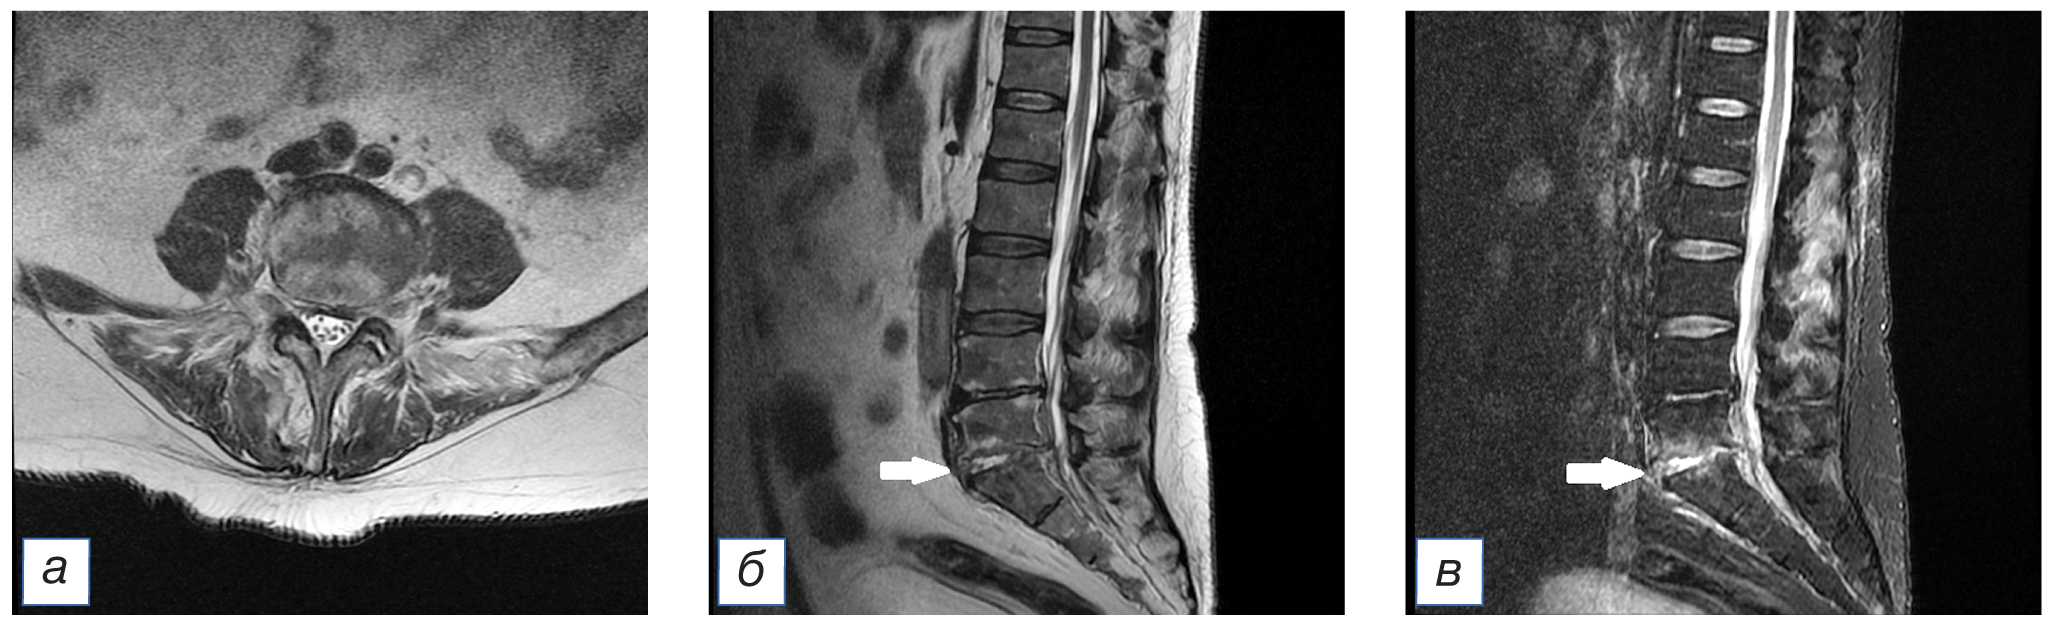

На 25-й день течения COVID-19 у пациента появилась умеренная боль в поясничной области, которая была расценена как проявление неспецифической скелетно-мышечной боли спондилогенного происхождения. Через несколько дней боль в пояснице внезапно приобрела очень интенсивный характер, что стало поводом для повторного выполнения МРТ поясничного отдела позвоночника, где были выявлены признаки выраженных воспалительных изменений диска L4–L5 по типу спондилодисцита и отек паравертебральных мягких тканей (рис. 4). После консультации пациента нейрохирургом была назначена антибактериальная терапия (см. табл. 1) с хорошим клиническим результатом.

Рис. 4. Тот же пациент: магнитно-резонансная томограмма поясничного отдела позвоночника: а — аксиальный срез в режиме Т2-FLAIR на уровне L4–L5; б — сагиттальный срез позвоночного столба в режиме T2-FLAIR. Стрелкой (б) указан очаг спондилодисцита. / Fig. 4. The same patient: magnetic resonance imaging of the lumbar spine: а — axial slice in T2-FLAIR mode at the L4–L5 level; б — sagittal slice of the spinal column in T2-FLAIR mode. The arrow (б) indicates the focus of spondylodiscitis.